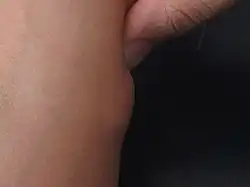

| Lipoma on forearm | |

A lipoma is a benign tumor made of fat tissue.[1] They are generally soft to the touch, movable, and painless.[1] They usually occur just under the skin, but occasionally may be deeper.[1] Most are less than 5 cm (2.0 in) in size.[2] Common locations include upper back, shoulders, and abdomen.[4] It is possible to have several lipomas.[3]

- Superficial subcutaneous lipomas, the most common type of lipoma, lie just below the surface of the skin.[13] Most occur on the trunk, thigh, and forearm, although they may be found anywhere in the body where fat is located.[14]